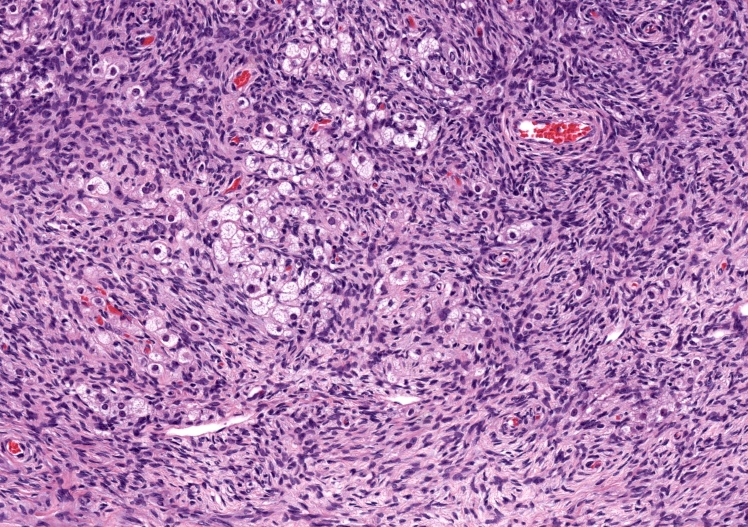

The image above represents a section of a well circumscribed, yellow, cystic nodule seen on gross examination of the ovary. The cells are positive for inhibin and calretinin. Which statement is correct?

C. The image represents a mature corpus luteum, which is a physiologic structure present in the luteal phase of menstruation. The constituent cells are polygonal with abundant, pale, eosinophilic cytoplasm representing the luteinized granulosa cells. The round nucleus contains 1 or 2 large nucleoli. These cells usually stain similar to steroid hormone producing cells and are typically positive for inhibin and calretinin.